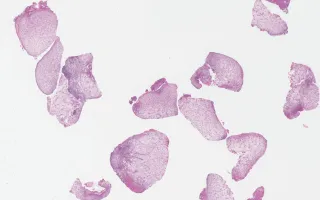

Nasal Cavity, Langerhan cell histiocytosis, H&E stain

2 year old male, presented with nasal polyps and multiple bone lesions.

Langerhan cell histiocytosis (LCH) is a rare histiocytic disorder, believed to represent a clonal proliferation of Langerhan cells. It has been historically referred to as histiocytosis X, Hand-Schuller-Christian disease and Letterer-Siwe disease. The multisystem/multifocal form predominantly affects children with a male predominance. It commonly presents with lytic bone lesion(s). However, it can also involve skin, liver, spleen, lymph node, and bone marrow. Microscopically, the neoplastic cells have a “coffee-bean” appearance with elongated nuclei and nuclear grooves, along with abundant eosinophilic cytoplasm. The Langerhan cells are embedded in a milieu composed of variable number of eosinophils, neutrophils and small lymphocytes. These cells express CD1a, langerin (CD207), and S100 protein. In this case, within the fragments of the nasal polyp resection, there are numerous Langerhan cells and eosinophils within a loose, edematous inflammatory mucosa.

This slide shows H&E stain. See related content for CD1a and S100 stains.